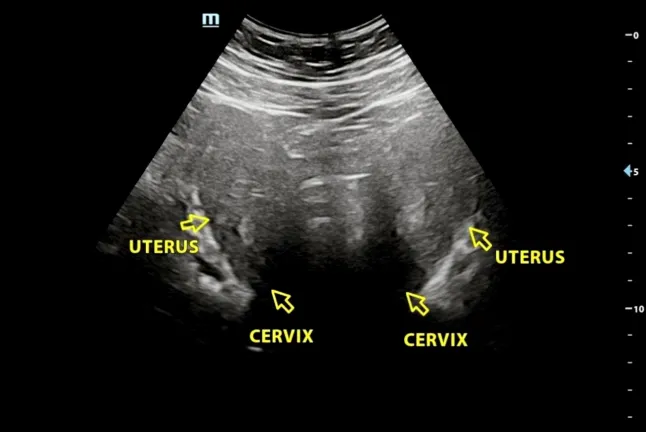

L’utero bicorporeo completo è una malformazione congenita dell’utero. È caratterizzato da una profonda divisione del corpo uterino in due cavità separate, completamente distinte, a causa di una mancata fusione dei dotti di Müller durante lo sviluppo embrionale.

Secondo la definizione dell’International Society of Ultrasound in Obstetrics and Gynecology, questa condizione si verifica quando l’incisura esterna del fondo uterino supera il 50 per cento dello spessore della parete uterina, determinando una separazione completa.

In termini semplici, l’utero non si sviluppa come un’unica struttura, ma rimane diviso in due.

Durante la laparoscopia, i medici hanno potuto osservare con precisione la struttura del suo utero, confermando la diagnosi di utero bicorporeo completo.

Ellie, in realtà, aveva già avuto un sospetto. Nell’ottobre 2024, mentre era in lista d’attesa, aveva pagato una ecografia privata che sembrava indicare la presenza di due colli uterini.